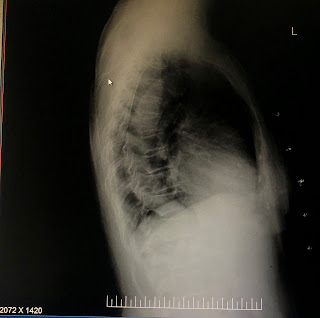

B/L chest X-ray lateral view